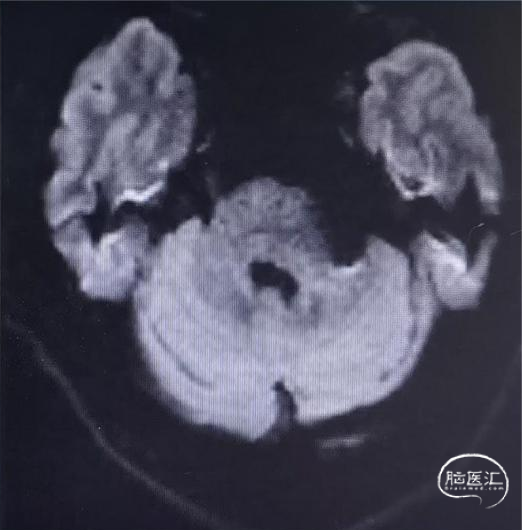

辅助检查

术后头颅磁共振;DWI项未见新发梗死灶。

磁共振管壁成像